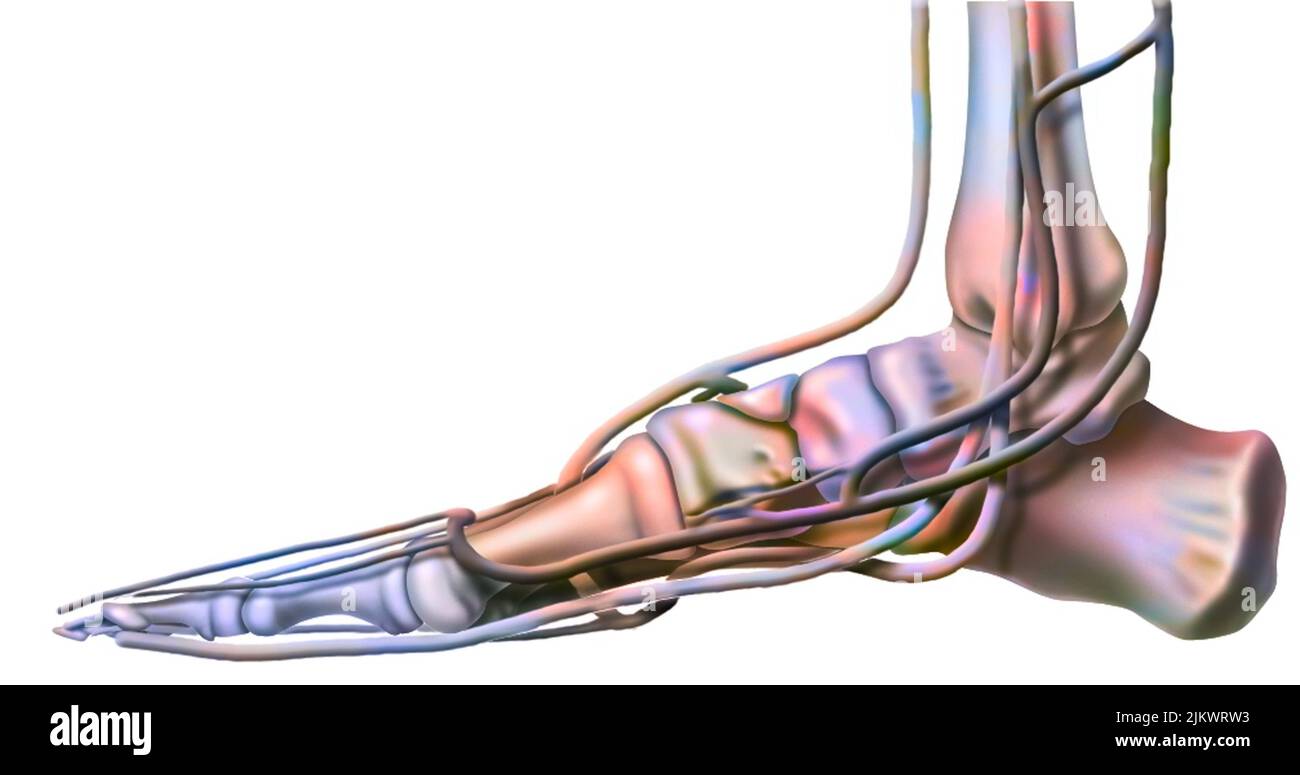

RF2ABM669–La médecine et les soins de l'illustre le tableau, les droits de l'anatomie du pied : Peau et tissus ectodermaux, os, muscles nerfs, vaisseaux sanguins

RF2JKN2D2–OS de la cheville humaine, position correcte os de la cheville humaine. Illustration Anatomy Health Care.

RFTCW7GT–L'articulation de la cheville, les tendons de la cheville anatomie pied eps vector illustration infographie 10